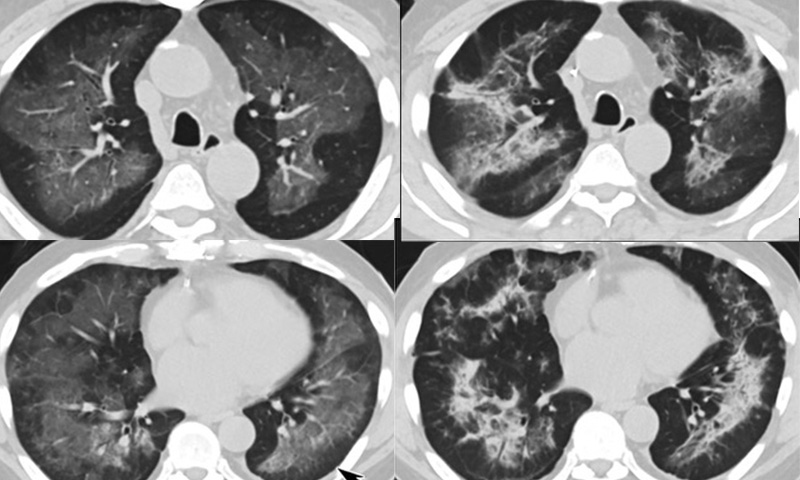

It's possible that some of the patients of the mysterious vaping-related lung disease that swept through all ...